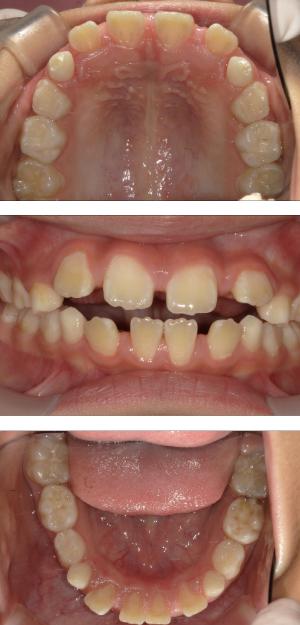

バイオブロック矯正(顎顔面口腔育成治療)

矯正治療は大人になって始めるよりも子どもの頃から始めた方が確実に良い結果をもたらします。成長が盛んな子供の時期に、顎や顔の成長を利用しながら治療ができる大きなメリットがあるからです。当院では、非抜歯矯正を推奨しておりバイオブロック矯正を取り入れています。

バイオブロック矯正の考え方は歯並びが悪くなる原因にアプローチする治療法になります。

舌の位置や口呼吸から乱れてしまった下顎の後退を正し、顎顔面が本来あるべき位置へと誘導させていく治療です。

- 歯並びの改善

治療開始年齢

6.7歳以降~10歳前後まで

(歯の生え変わりスピードによって個人差はございます)